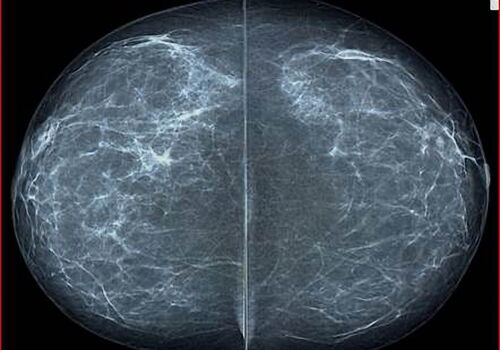

Es werden pro Mammogaraphieuntersuchung in der Regel pro Brust 2 Aufnahmen und unterschiedlichen Richtungen angefertigt. Hier seitlich/schräge Abbildungen -

Hier die andere Aufnahmen mit senkrechter Abbildung